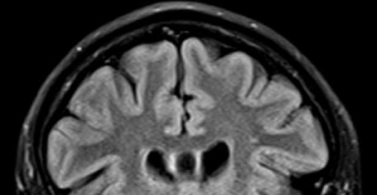

The methodologies used by these authors were weak and not scientific. Adrian Raine –in his book– tested some temporary employee and paid them money to tell him stories about the crimes that they did in the past! All of this study is protected by taking protection from the authorities. So, they told him about many murders, rapes, arm robberies, etc. Do the reader of this paper see how weak that methodology is? He paid people to lie to him and tell him some horror stories like a group of children on the camp fire. This is how pathetic their “research” methodologies are! Paying people to tell you fairy tales. Then Raine did an MRI scan for their brains and their brain appeared normal. People with antisocial behavior have lower brain volume. But Raine’s sample of supposed anti-social psychopaths have normal brains. What a waste of money and resources! Raine claimed that cavum septum pellucidum is a sign in psychopaths, neglecting that it is a normal anatomical variation that exist in all fetuses and fuse in 85% and remain opened in 15% of population see (Figure 1). Raine claim that 15% of humans are psychopaths, so what he suggests? Eliminate 15% of the people with these normal anatomical variations. He even calls them “biological high risk”!

Figure 1: An MRI scan sagittal section with a closer look to the cavum septum pellucidum which Raine claim that is a sign of pychopaths!